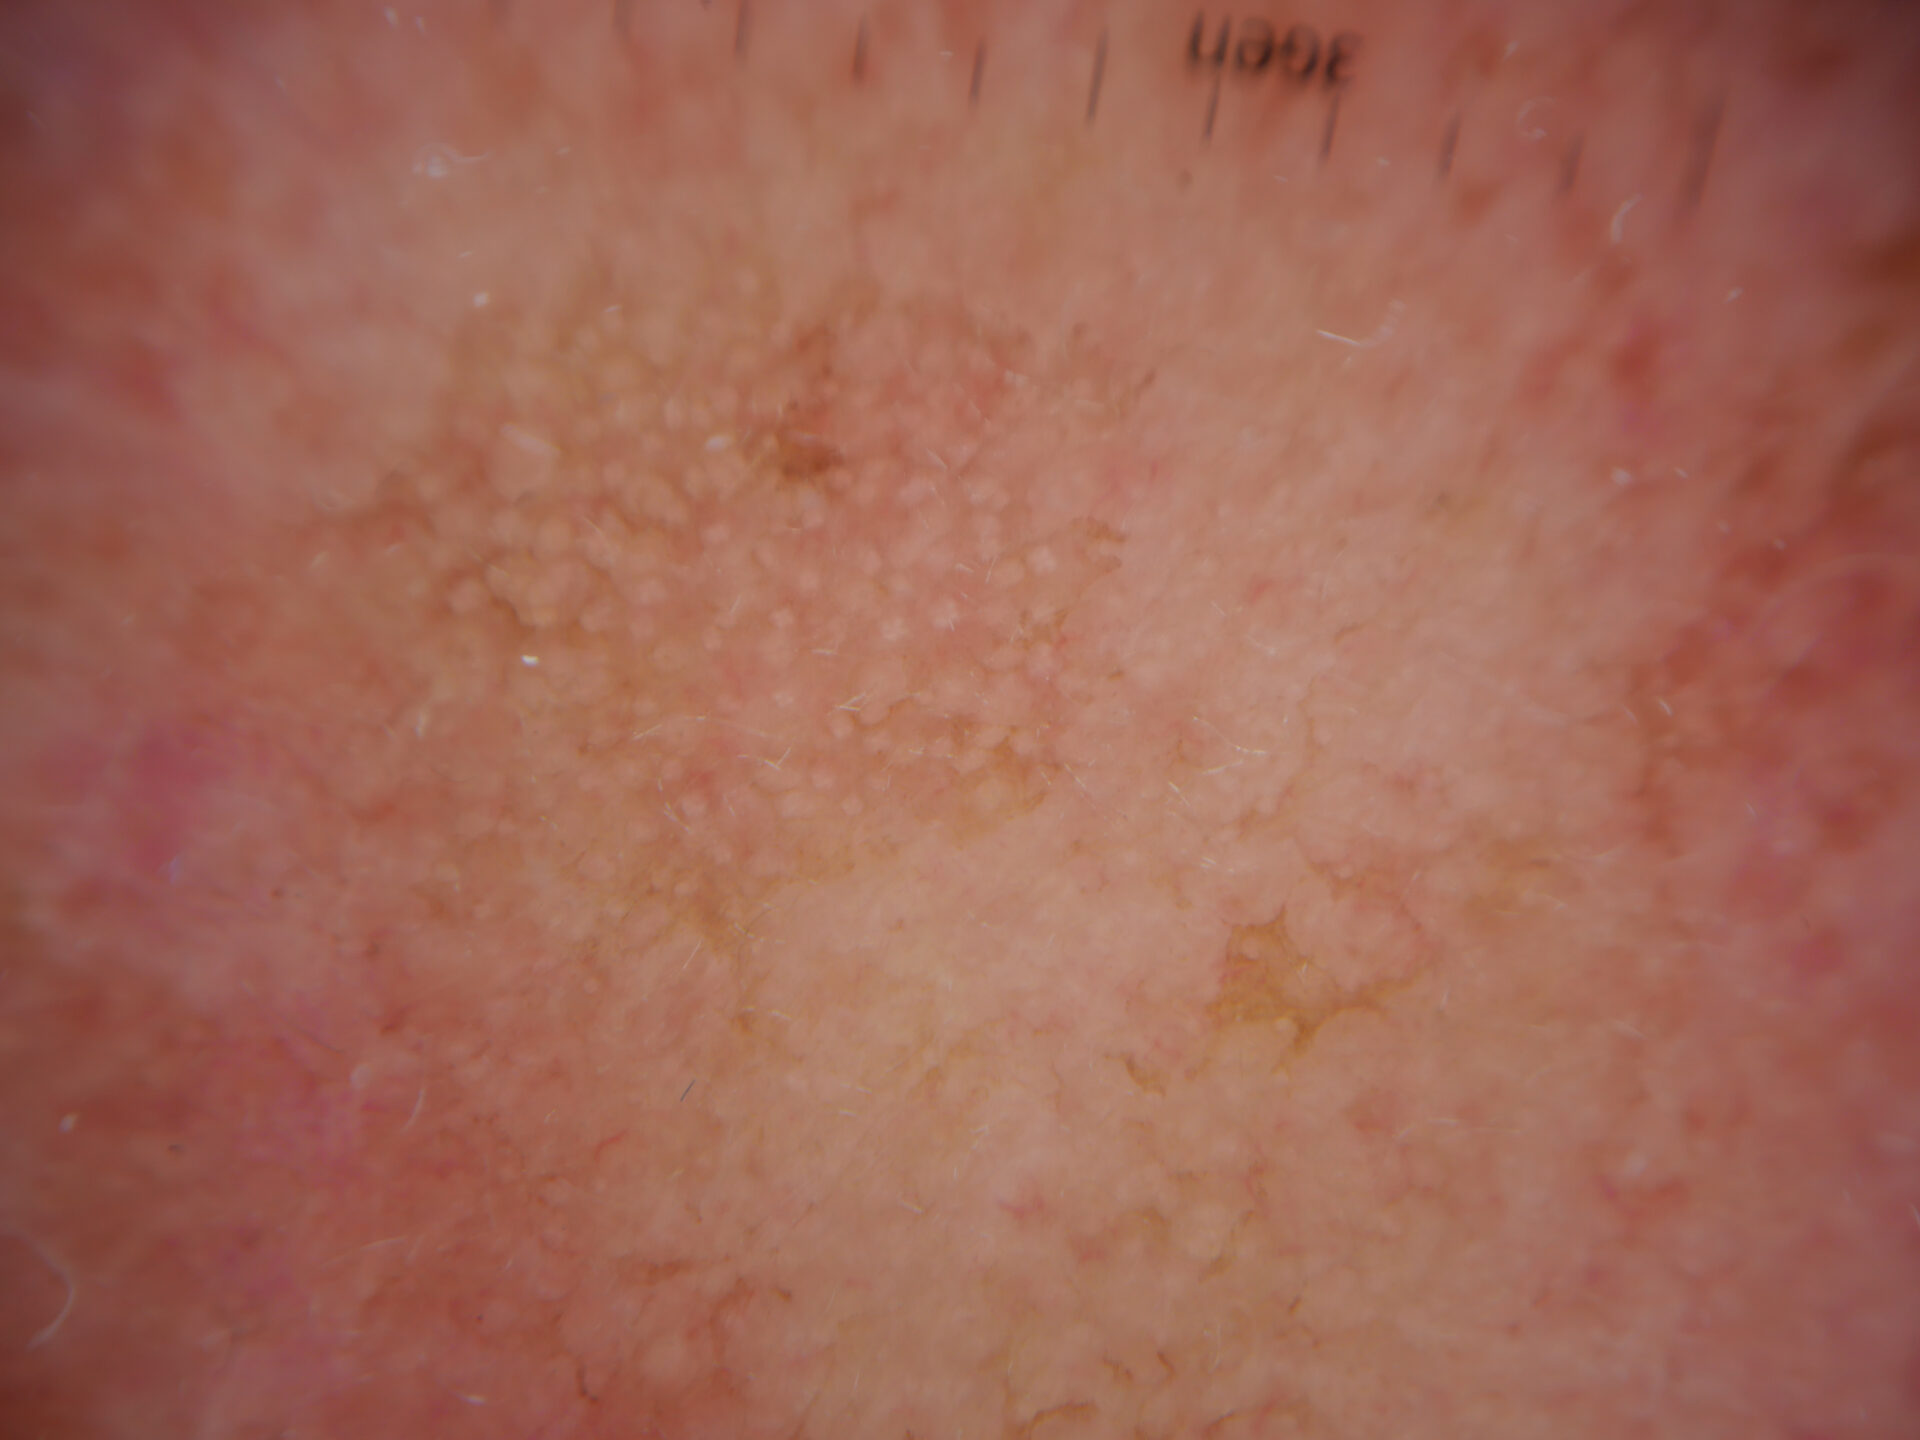

Actinic Keratosis (AK) Photos

Actinic keratosis on posterior torso. Photo: International Skin Imaging Collaboration at isic-archive.com